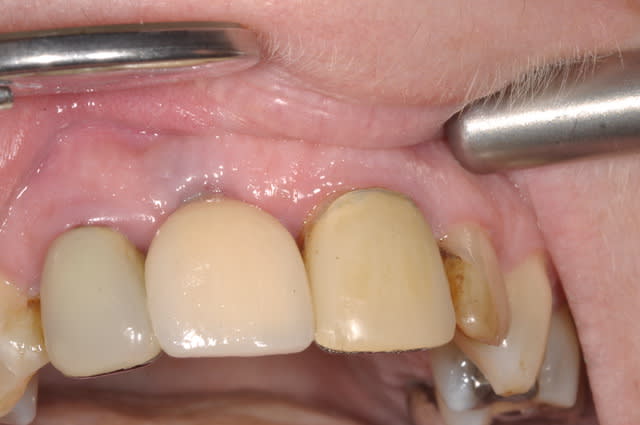

comme promis Céramic

Controle et pose 15 jours apres du fx moignon vendredi dernier entre les deux L'APN en panne

provisoire avec diastème en bouche, suis pas certain que cela va lui plaire

Moi c'est le collet qui ne me plait pas,donc une provisoire çà m'arrange

les 12 et 21 sont toujours d'avant 1992!

CCM posée il y a un mois

plus de diasteme, c'était bien la peine, l'hygiene toujours au top et la gencive a adoré l'aller retour

par contre l'implant lui RENDRA SERVICE